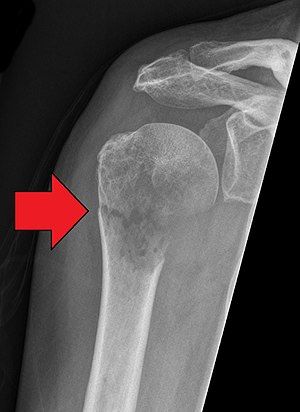

Pathological Fracture - आजारामुळे हाडे कमजोर होऊन तुटणे.